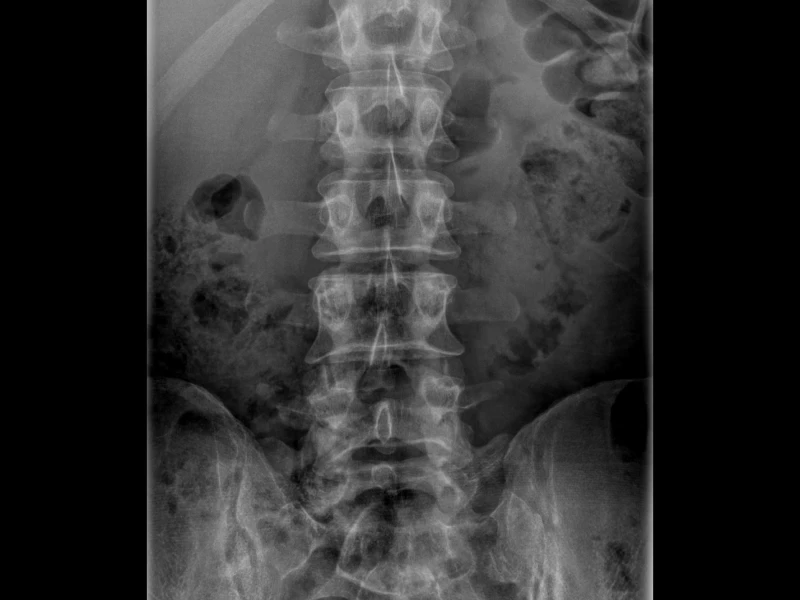

1. Empezá por la base: la radiografía (Rx)

La radiografía suele ser el primer contacto del médico no especialista con la imagen. En el post vas a ver lo esencial: cómo se forma la imagen, qué degrada la calidad y por qué aparecen errores típicos.